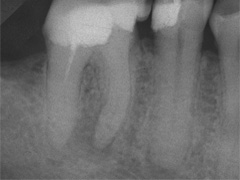

Dieser Zahn wurde schon geraume Zeit zuvor von einer Kollegin im Notdienst eröffnet und anschlies­send mit einer aufwendigen Amal­gamrestauration ästhetisch an­sprechend wieder verschlossen. (Bild 1) Uns blieb noch WK/WF, was bei massiver Überstopfung der hin­teren Wurzel auch gelang (Bild 2).

"Überstopfen ist immer noch besser als Unterstopfen" laut Koçkapan. OK, hier wurde des Guten aber ganz eindeutig zuviel getan.

Also direkt neben dem Zahn das Zahnfleisch ein wenig angehoben und zur Seite gedrängt und dann mit einem scharfen Löffel den Überschuss vollständig entfernt.

Schon 8 Monate später ist eine deutliche Verbesserung der Gesamt­situation unverkennbar (Bild 3). Verlorengegangene Knochensubstanz wurde in Teilen schon wieder aufge­baut, doch ist noch gar nichts entschieden. Schaun mer also ma'.

Abrechnungstechnisch hat der Mut zur WR an 38 gefehlt, deshalb nur EXZ1.